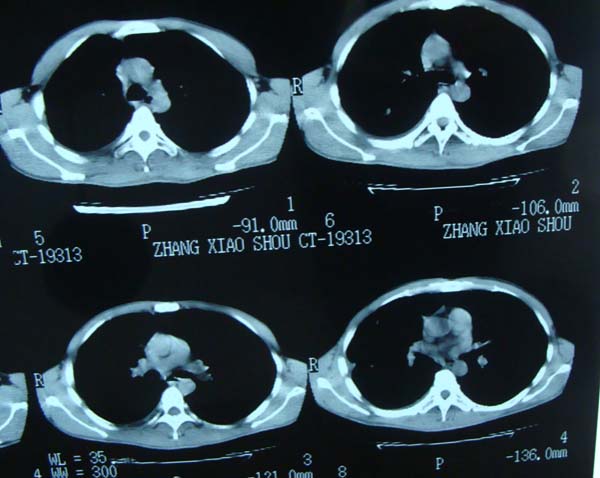

标题: CT15132:男,26岁。建筑混凝土工人。发热。咳。 [打印本页]

标题: CT15132:男,26岁。建筑混凝土工人。发热。咳。

右肺继发型肺结核,右侧胸腔积液、胸膜肥厚粘连。

胸膜肥厚

右肺及胸胸膜多个结节多考虑转移瘤,右侧胸水,结核次之。

右肺继发型肺结核,右侧少量胸腔积液、胸膜肥厚。